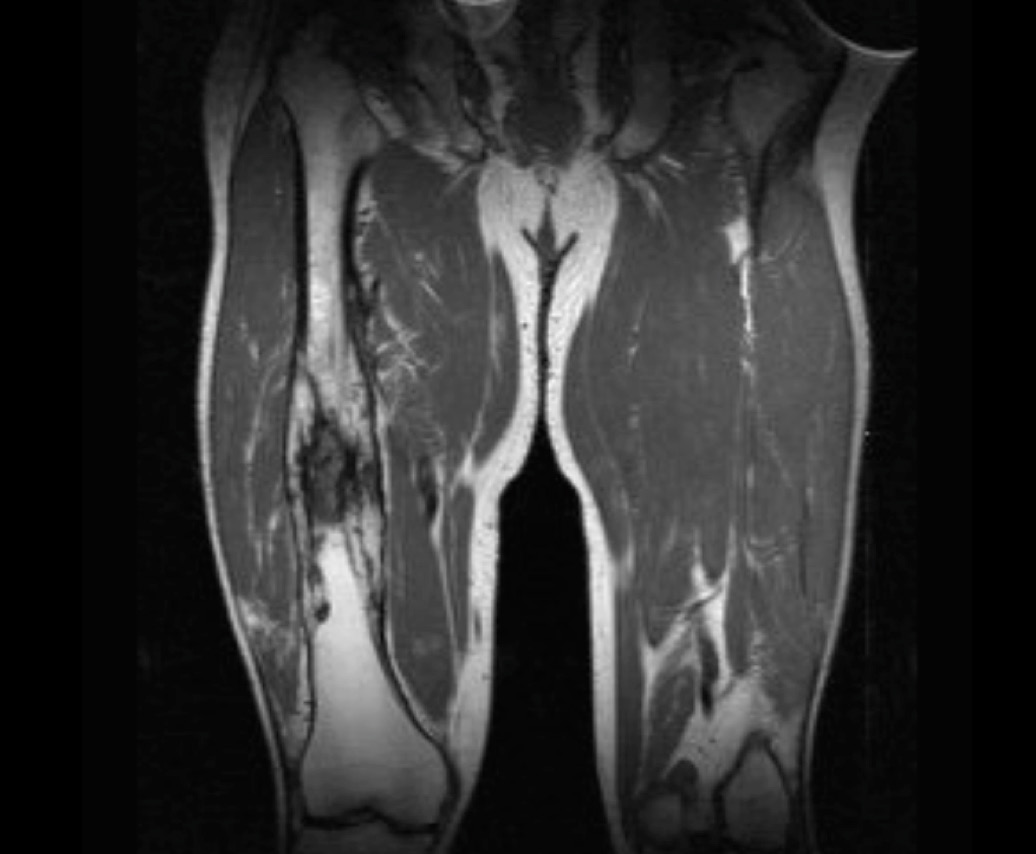

This gentleman has chronic osteomyelitis of the femur resulting in mal-union and a central sequestrum (dead infected bone) with surrounding involucrum (new bone growth as a result of infection). These features are better appreciated on magnetic resonance imaging (MRI) – and a sample image is shown below.